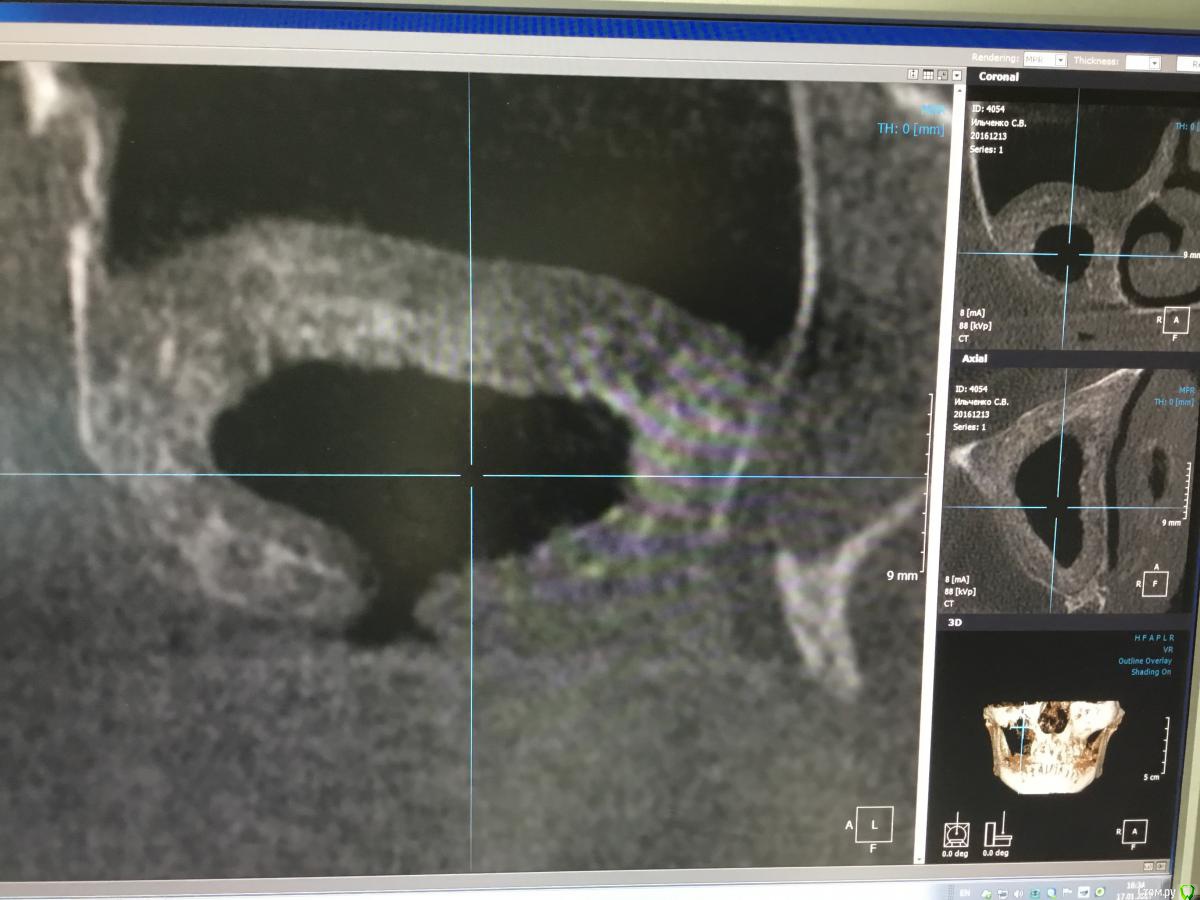

Bier Опубликовано 17 января, 2017 Автор Поделиться Опубликовано 17 января, 2017 7 мес, скорее расслоение, был бы разрыв, все бы в пазуху улетело. Ссылка на комментарий

Bier Опубликовано 17 января, 2017 Автор Поделиться Опубликовано 17 января, 2017 как думаете, почему не весь графт отработал? На установке болтов окно после синуса "окостенелое" было?потому что произошла неполная отслойка слизистой пазухи во время операции. Она подвернулась или расслоилась. 1 Ссылка на комментарий

voff Опубликовано 26 января, 2017 Поделиться Опубликовано 26 января, 2017 синус в синусе Ссылка на комментарий